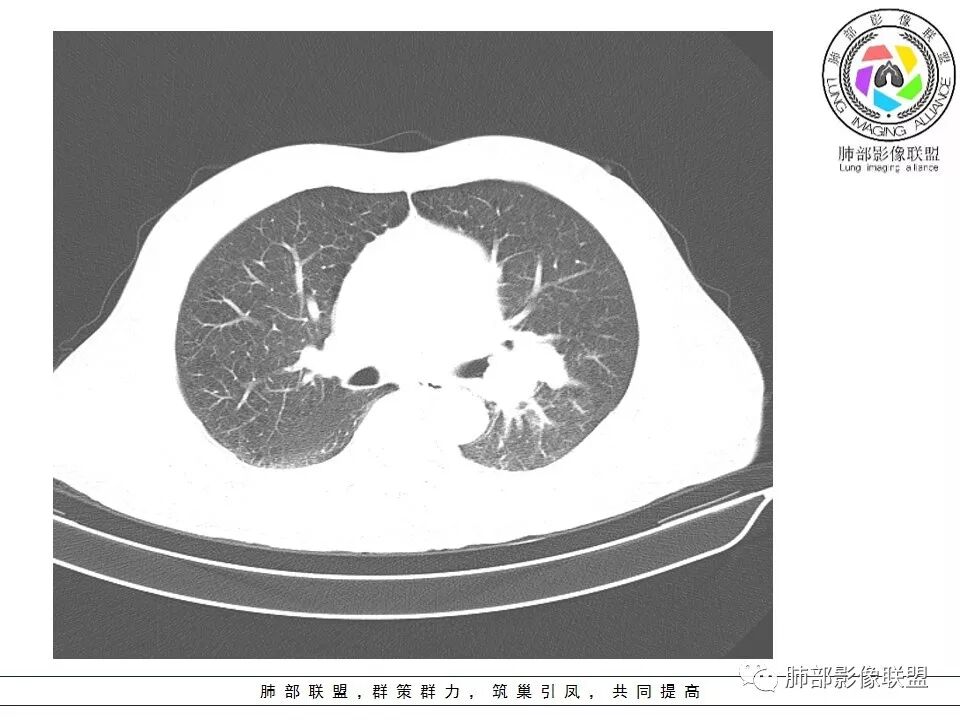

老年男性咳嗽,左下近肺门团块影,不规则强化伴坏死,左下肺静脉、支气管旁淋巴结转移受压、并侵犯左下支气管,考虑鳞癌,鉴别小细胞。

男,70岁,左下肺肿块影,分叶,增强有较大范围坏死,左肺门肿块影,跨叶,包绕支气管与肺门血管,致其狭窄考虑为淋巴结肿大,综合考虑为恶性肿块,鳞癌并左肺门淋巴结转移

肺门淋巴结有肿大,支气管内有肿物,这么大病灶没有坏死,我考虑神经内分泌癌或者小细胞肺癌。鳞癌不符合没看到明显阻塞

老年男性,咳嗽主诉,胸部ct左侧肺门新生物,支气管阻塞,不均匀强化,伴淋巴结肿大,考虑鳞癌,鉴别小细胞肺癌。

老年男性,左下占位,类圆丶浅分叶,无毛刺及胸膜凹陷征,各支气管狭窄,增强不均匀强化,左肺门淋巴结肿大考虑恶性,小>鳞

患者老年男性,以咳嗽就诊,胸CT:左肺下叶占位,病灶呈膨胀性生长,左肺下叶气管明显狭窄,病灶边缘光滑,并可见分叶,增强可见病灶内低密度区,病灶边缘强化。考虑恶性,鳞?肉瘤?

左下肺团块影,不规则强化伴坏死,左下肺静脉、支气管旁淋巴结转移,并侵犯左下支气管,考虑恶性病变,小细胞?

左肺主支气管下肿块,病变包绕并向腔内生长,无阻塞性肺炎,内部可见穿行血管,增强后可见实性明显强化,纵隔淋巴结肿大,老年男性,考虑:神经内分泌癌(类癌、小细胞癌),淋巴瘤,鳞癌

病史:男,70岁,咳嗽;影像:肺门淋巴结,淋巴结内血管毛糙不规则,静脉期,转移大,左心房左下静脉下支是否有累及。主体病灶,呈扇形,沼泽样,指状突起。肺气肿并不明显,左侧少许,左上叶支气管狭窄,肺窗点状凸起,纵膈窗并没有,考虑淋巴结压迫所致。老王曾经说过,小细胞来不及跑得快,胸膜目前没有积液是否是这个原因?诊断:恶性,小细胞肺癌;鉴别:鳞癌,不太像,其他神经类分泌恶性肿瘤;处置:经皮穿刺或EBUS。

左下肺占位性病变,伴肺门淋巴结肿大,强化示不均匀明显强化,可见边界不清坏死区,考虑恶性肿瘤!病灶缺乏分叶及毛刺,整体圆顿,病理倾向大细胞!

左下肺肿块,不均匀强化,其内可见坏死或粘液,更多考虑坏死,左下肺支气管堵塞,左肺门多发肿大淋巴结,左下肺癌,鳞癌可能性大鉴别于小细胞癌

病灶从外向里长,气管狭窄,血管受侵犯,肺门纵膈淋巴结肿大,考虑恶性,首先考虑小细胞癌

左下肺占位伴肺门淋巴结肿大,病灶呈膨胀性生长,左肺下叶气管明显狭窄推移,病灶边缘光滑,并可见分叶,增强可见坏死,病灶边缘强化,阻塞性肺炎不明显,恶性没问题,考虑低分化腺癌,鉴别神经内分泌肿瘤,无冰冻感觉,坏死明显,小细胞不支持,排除大细胞与类癌

老年男性,症状轻。左肺下叶类圆形肿块,边界清楚,分叶不明显,其内无空泡征,边缘无毛刺及胸膜牵拉,远端无阻塞性肺炎。左肺门影增大。增强扫描左肺下叶肿块可疑轻度强化(无平扫对比),局部见小尾巴征。左肺门区见不规则形团块,似多个结节融合,肺动脉受压穿行于病灶中,形成冰冻肺门感觉,局部层面似见肺门区团块与左肺下叶肿块相连。综合考虑小细胞肺癌(SCLC)。

左肺下叶肿块,边缘膨隆,分叶略浅,占位效应明显,远端没有明显花花草草,其内部不均匀强化,坏死边界不清,可见受累的强化血管穿行,是否有钙化?没有平扫,不清楚;同侧肺门淋巴结受累,包绕支气管生长,并突入下叶支气管,导致管腔闭塞及狭窄,考虑恶性没问题,肿瘤既有由外向内生长侵犯又有冰山征的感觉,小>类癌>低分化腺>鳞

病灶从外向内生长,气管狭窄,血管受侵犯,肺门纵膈淋巴结肿大,考虑恶性,腺癌。鉴别小细胞肺癌。

左下肺占位,边缘分叶彭隆,远端无明显阻塞性炎性,考虑外朝内生长为主,增强扫描边缘及病灶内均可见强化,血管破坏。考虑恶性,间叶组织来源,肉瘤?

左肺下叶肿块,内部坏死明显,整体从外向内生长,下叶支气管及舌叶支气管被包绕生长,肺门区淋巴结肿大,坏死。远端无明显阻塞及不张,综合来看,恶性肯定,肺癌,整个病灶有分别有支持小细胞、鳞癌,腺癌及肉瘤样癌的地方,但又不典型,以低分化腺癌或肉瘤样癌或混合性癌(腺癌小细胞混合,低化分腺鳞癌混合),神经内分泌癌可能性大,单纯的鳞癌或小细胞癌有可能,但确实不典型了。至于间叶来源的恶性肿瘤,很少这样从向外内生甚至包绕支气管壁生长,再加上相对罕见,可能性小。

腔外浸润为主,腔内无明显堵塞,原发肿块推移支气管为主,边缘光滑,轻微分叶,肺门引流区淋巴结肿大,而纵隔淋巴结无明确受累,综合考虑,癌:低分化腺癌?大细胞癌?肉瘤样癌?间叶组织肿瘤:肺肉瘤,罕见

左肺门乱乱的,有血管受压表现,有支气管腔内占位表现,肺门淋巴结肿大肯定是有的;左肺下叶见一巨大包块,边缘光滑,内侧又一个切迹,考虑是病变受到了小叶间隔阻挡造成的其内部大部分不强化,但有局部一小片强化;壁不均匀环形强化,总体较薄;周围没有阻塞性肺炎,感染性病变应该是不考虑的,因为周围清楚,也没有感染的症状,还是考虑肿瘤性病变;关键是它边缘光滑,内部应该是坏死,但有强化提示坏死不彻底,这么大了,边缘恶性征象不明显,不符合腺癌,鳞癌呢也不太符合,阻塞性肺炎没有,坏死太明显了,这么大,边缘光滑,坏死明显,符合肉瘤和肉瘤样癌,不除外小细胞肺癌

南边:病灶分为两大块,外围囊实性大肿块,支气管关系不密切,内带多发淋巴结,侵犯支气管、肺血管,恶性没问题,按理间叶为主,或不典型的癌,这不是一个中央型的肺癌,是外朝内进展的,奇怪的是边界这么清楚光滑,一般癌肉瘤、肉瘤类多,其次才是癌,远端也没有阻塞,大方向是这样,恶性,间叶来源?或者混合,恶性程度较高,鉴别就是结核,因为结核是妖

1.左肺下叶近肺门区肿块,肿块外围大,内带小,提示外围向中央生长,符合周围型SCLC沿支气管方向生长。

2.病灶边缘光滑,未见明显分叶、毛刺,符合神经内分泌癌、癌肉瘤及间叶来源肿瘤。

3.病灶内密度偏低,穿行血管未见明显异常,轻度不均匀强化,为乏血供病灶。病灶内可疑坏死区,未见空洞;乏血供符合SCLC,但坏死区不符合。

4.病灶区支气管以受压推移为主,管腔不规则,腔内通而不畅,提示病灶粘膜下为主,符合SCLC迁徙蔓延或间叶来源肿瘤。

5.病灶内有血管走行,血管局部受压,但是强化考虑为乏血供,提示病灶内肺动脉并不是供血血管,只是病灶侵袭性强把血管包埋而已,为血管包埋征;血流面光滑,血管包埋符合SCLC。

6.左肺门淋巴结肿大,与病灶局部融合分界不清,呈冰冻肺门;而纵隔内未见肿大淋巴结,冰冻肺门符合SCLC,但是病灶主体那么大,纵隔内没有明显肿大淋巴结,不是很符合SCLC娘小崽大的特点。

7.未见明显阻塞性炎症及阻塞性肺不张,更加提示病灶从外围向中央侵犯,符合SCLC罕见阻塞性肺不张。